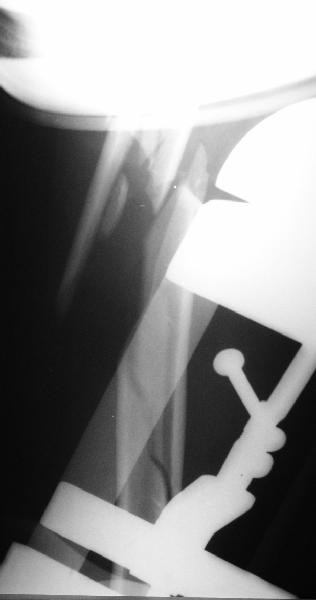

I just did this attached case, using 90 degrees angled blade plate, and this would be my preference in all similar cases.

Although we can not see exactly the head piece, and assuming that there are not signs of infection, my suggestion would be to do some type of "bridging" procedure : implant fixation in head piece and distal main fragment, and the rest to be left on its soft tissue attachments (living bone graft).